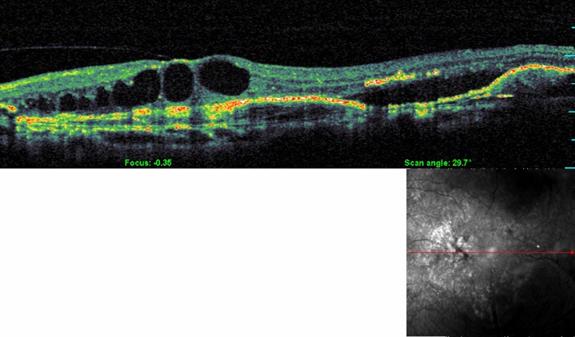

Optical Coherence Tomography (OCT)

OCT is a non-radiation mode of scanning that utilizes certain light waves for the scan.

OCT can show the retinal layers almost as if in biopsy (layer by layer). The resolution of the Spectral OCT scan available in MEH is 5 microns. Such highly precise scans help your doctor diagnose your AMD quite effortlessly.

• leading eye hospital for AMD treatment

Normal OCT

• top eye hospital for AMD

OCT in AMD

• best eye hospital for macular degeneration in Kerala

OCT is the most sensitive scan for monitoring the progress of AMD as well as for assessing the response to treatment.